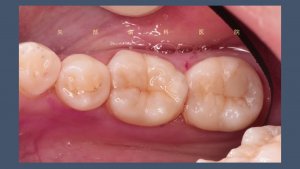

歯の形態の付与

手前の不良充填物の再治療とWSD(くさび状欠損)

今回は手前の第二小臼歯、第一大臼歯の再治療も行うこととなりました。第一大臼歯は咬合面に古いコンポジットレジンによる修復が行われていますが接着不良による剥がれが起こっているようです。また、唇側歯頚部のエナメル質のくさび状欠損がおこっています。

CRの再治療を行う際には古い充填物を全て取り切ることが重要です。接着がうまくいっていないために起こったので確実に古い充填物を除去しています。

くさび状欠損の充填と歯肉圧排

歯肉圧排糸という糸を歯ぐきのきわに挿入することで歯ぐきを押し下げることができます。

その後、形態修正と研磨を行い終了です。日々こういった精密治療を丁寧に行なっているのでかなり時間がかかってしまいます。患者さんには毎回、長時間お口を開けていてもらうので顎が疲れてしまって申し訳ないと思います。少しでも早く確実に治療が行えるように日々精進しています。